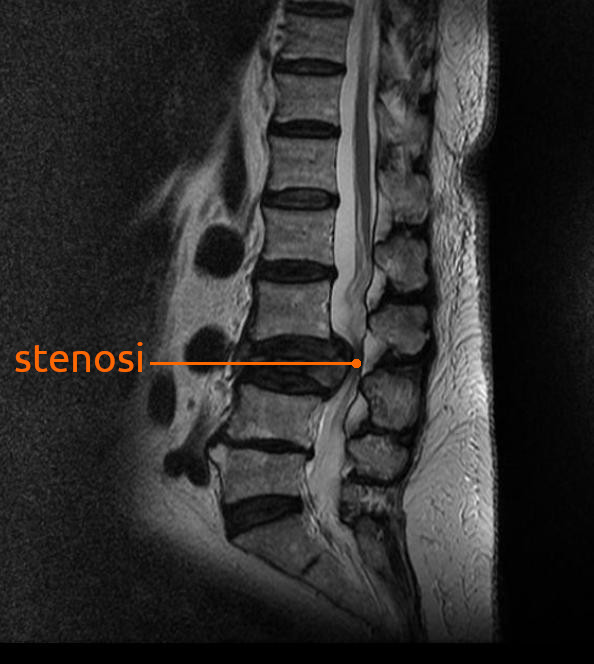

La stenosi vertebrale o spinale è un restringimento anomalo del canale spinale o del forame neurale che provoca una compressione del midollo spinale o delle radici nervose.

La forma più comune è la stenosi spinale lombare e la stenosi spinale cervicale. La stenosi spinale toracica è molto meno comune.

Nella stenosi lombare, le radici del nervo spinale sono compresse, il che può portare a sintomi di sciatica (formicolio, debolezza o intorpidimento che si irradia dalla parte bassa della schiena e nei glutei e nelle gambe).

- Fase Pcl: ad una fase edematosa e molto dolente, segue una fase di ricostruzione delle aree asportate con eccesso di tessuto che coinvolge il canale vertebrale. Recidive numerose causano un restringimento del canale e compressione di midollo spinale e radici (cervicale) o della cauda equina (lombare).